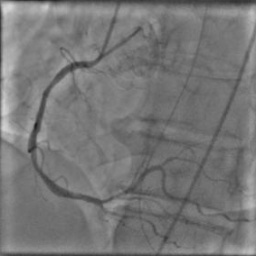

X-ray angiography is the most used imaging modality to visualise blood vessels for interventional purposes such as stenting of stenosed vessels or for diagnostic purposes such as assessment of myocardial perfusion or stenosis grading. To minimise ionising radiation exposure of the patient and medical personnel during image acquisition, low power X-Rays are used resulting in noisy and low contrast images. In the context of diagnosis, the main object of interest is the vascular tree, its branchings and variations in thickness. It is therefore necessary to accurately highlight the vessels in consecutive frames to reduce the noise and improve contrast. In addition, in interventional procedures, identifying interventional instruments (catheter, wires) is also needed in order to better plan and control their positioning. Efficiently discriminating between instruments and vessels as well as other anatomical structures that may have similar appearance is crucial during the interventions. Figure 1(a-c) shows an example of an angiogram sequence. Note large non-rigid motion between frames as well as the ambiguity between vessels and the catheter. Figure 1(e) shows a frame from a different sequence of the same patient but taken at different scan and angle and (f) shows a different patient. There is a significant difference in vessel as well as catheter locations in all three sequences, which we consider as independent examples. Figure 1(d) shows the ground truth segmentation of the first frame.

The dataset consists of anonymised fluoroscopy X-Rays of 26 different patients. The images were acquired during stent placement using a General Electric Innova 2000 system and stored according to standard medical protocol in DICOM format. In total the dataset includes 36000 frames corresponding to 365 distinct video sequences with an average of 98 frames each. Different sequences of the same patient were taken at different angles and stages of the procedure therefore they differ significantly as shown in Figure 1(c)(e)(f). Each frame is rescaled from to due to memory constraints.